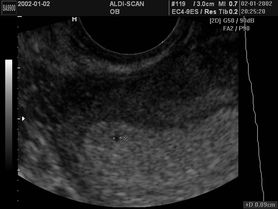

Płód w 5 tygodniu ciąży

Płód w 4 tygodniu ciąży

Pierwsze tygodnie ciąży – objawy, przebieg, badania